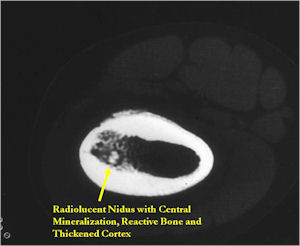

CT Scan:

- Well defined nidus with a smooth peripheral margin; +/- mineralization (CT more sensitive than XR and MRI for detecting mineralization); CT is better for detecting nidus in presence of exuberant sclerosis